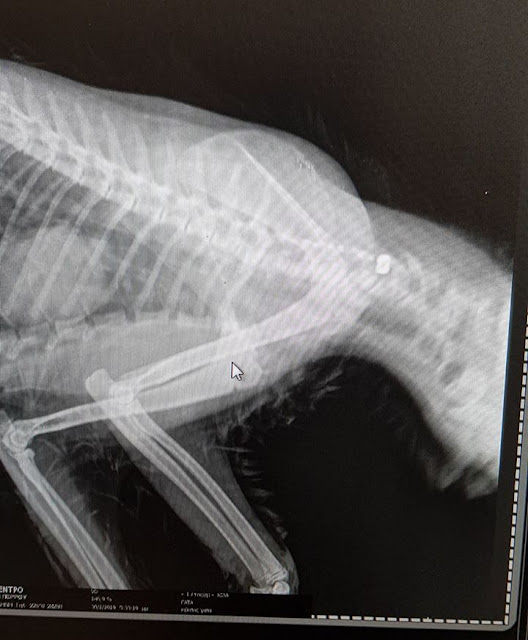

Το τραυματισμένο ζώο, μια αδέσποτη γατούλα, εντοπίστηκε και μεταφέρθηκε σε ιδιωτικό κτηνιατρείο όπου η ακτινογραφία έδειξε ότι έφερε βλήμα αεροβόλου όπλου σφηνωμένο στο λαιμό της, κοντά στην σπονδυλική στήλη.

Η κατάσταση του ζώου παραμένει κρίσιμη.